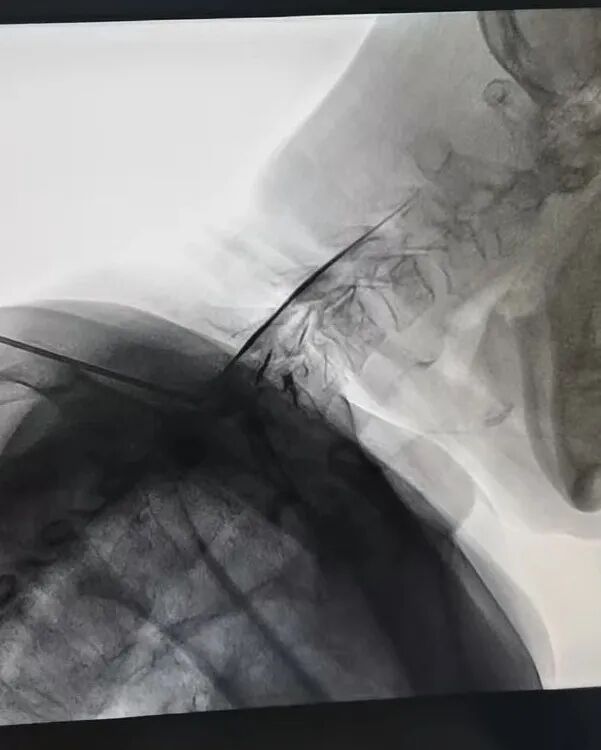

患者左女士,女,55岁,因颈肩部疼痛伴双上肢麻木、疼痛5年余,不仅白天受痛,晚上也睡不好,左女士备受折磨,生活质量差,焦虑状态。曾多次进行理疗治疗,当时有所减轻,稍劳累后或遇阴雨天气均会发作,近5年来,患者颈肩部疼痛及双上肢麻木、疼痛症状反复发作,该患者于2024年11月19日入住我院疼痛科,经外院颈椎核磁共振提示:颈椎3-7椎间盘突出,以5-6椎间盘突出为甚,对此疼痛科周理平主任带领他的团队对左女士进行了颈5-6椎间盘射频消融术+经皮颈5-6椎间盘胶原酶化学溶解术,术后左女士自觉疼痛明显减轻。

图片